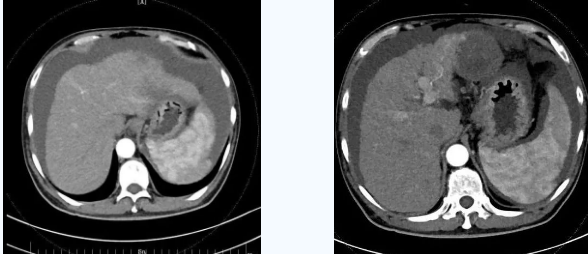

由于大量腹水、晚期肝癌加上尿毒癥等的綜合病癥,手術(shù)難度和危險系數(shù)都比平常增加了幾倍,面對這樣的情況,術(shù)前韓國宏院長帶著團隊反復(fù)分析討論,全面評估,在患者的各項指標(biāo)達到手術(shù)標(biāo)準(zhǔn)后,對患者實施了經(jīng)頸靜脈肝內(nèi)門腔靜脈分流術(shù)(TIPS),手術(shù)取得成功,術(shù)后患者恢復(fù)良好。

術(shù)后一個月秦先生來院復(fù)查,腹水已明顯較前減少,精神和飲食較術(shù)前明顯好轉(zhuǎn)。

韓國宏院長介紹,TIPS原理是采用特殊的介入治療器械,在X線透視導(dǎo)引下,經(jīng)頸靜脈入路,建立肝內(nèi)的位于肝靜脈及門靜脈主要分支之間的人工分流通道,并以金屬覆膜內(nèi)支架維持其永久性通暢,達到降低門脈高壓后減少腹水產(chǎn)生,控制和預(yù)防食道胃底靜脈曲張破裂出血的目的。